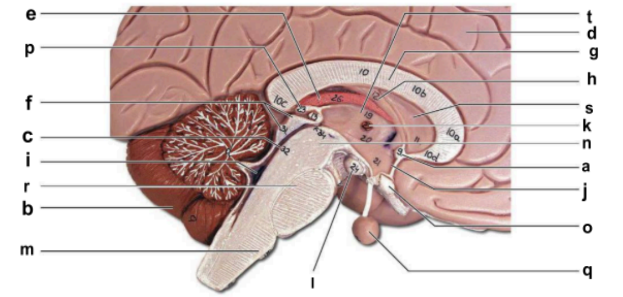

Identify the structure labeled “a” in the image.

anterior commissure

Identify the structure labeled “b” in the image.

cerebellum

Identify the structure labeled “c” in the image.

cerebral aqueduct

Identify the structure labeled “d” in the image.

cerebral hemisphere

Identify the structure labeled “e” in the image.

choroid plexus

Identify the structure labeled “f” in the image.

corpora quadrigemina

Identify the structure labeled “g” in the image.

corpos callosum

Identify the structure labeled “h” in the image.

fornix

Identify the structure labeled “i” in the image.

fourth ventricle

Identify the structure labeled “j” in the image.

hypothalamus

Identify the structure labeled “k” in the image.

interthalamic adhesion

Identify the structure labeled “l” in the image.

mammilary body

Identify the structure labeled “m” in the image.

medulla oblongata

Identify the structure labeled “n” in the image.

midbrain

Identify the structure labeled “o” in the image.

optic chiasma

Identify the structure labeled “p” in the image.

pineal gland

Identify the structure labeled “q” in the image.

pituitary gland

Identify the structure labeled “r” in the image.

pons

Identify the structure labeled “s” in the image.

septum pellucidum

Identify the structure labeled “t” in the image.

thalamus